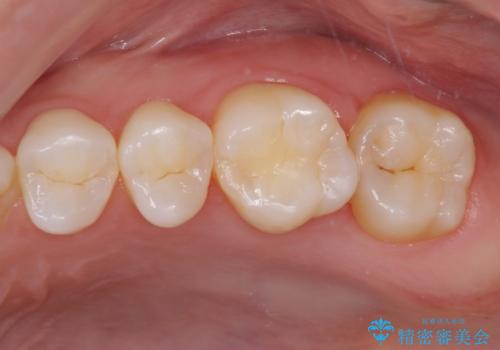

- 奥歯にフロスが引っかかるようになり、虫歯ではないかとのことで来院された患者様です。

レントゲン写真より、1番奥の歯に虫歯があることが分かりました。